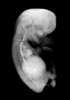

Human Embryo

Carnegie Stage 23 (56 post-ovulatory days)

Most embryos at stage 23 are approximately 56-57 postovulatory days old and measure 23-32 mm in length. Distinguishing criteria for this stage include fusion of the eyelids at the medial and lateral margins, clear distinction of the subdivisions of the upper and lower limbs, the forearms appear at or above the level of the shoulders, the superficial vascular plexus of the head is very close to the vertex, and the external genitalia are well developed but not always sufficiently to distinguish the embryo's sex.

(NOTE: These specimens are late stage 23.)